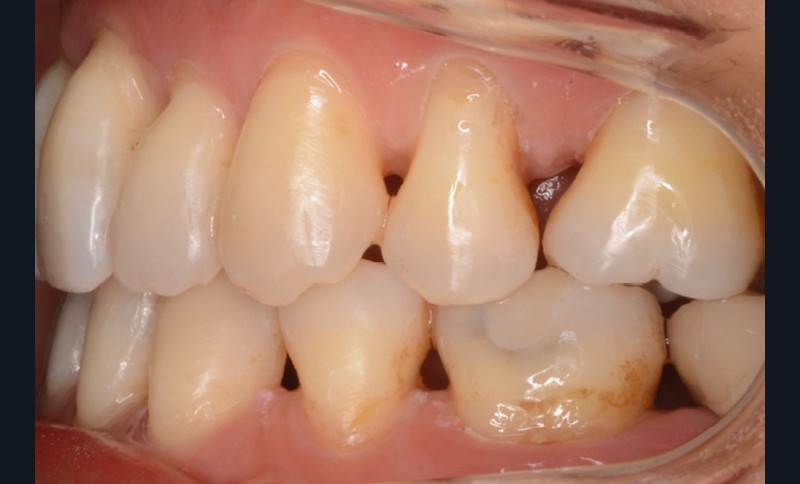

La patiente présente par ailleurs une parodontite chronique modérée stabilisée (Stade 3, grade C selon la classficaiton de Chicago 2018) et bénéficie d’une maintenance trimestrielle chez son parodontiste, qui nous donne son accord pour le traitement orthodontique moyennant un suivi très régulier.

Sur le plan dentaire, la patiente est en classe III droite et gauche, canine et molaire de 6 mm, avec une occlusion inversée antérieure localisée à 11, 12 et 22. Elle présente une dysharmonie dents-arcades sévère, une agénésie d’une incisive mandibulaire est à signaler, et les troisièmes molaires ont été extraites à l’âge de 21 ans.

Au niveau fonctionnel, on note un bruxisme statique avec contact permanent entre les dents maxillaires et mandibulaires. La patiente présente des prématurités en relation centrée sur les incisives, le guidage en propulsion est perturbé et des interférences multiples sont retrouvées en latéralités droite et gauche.